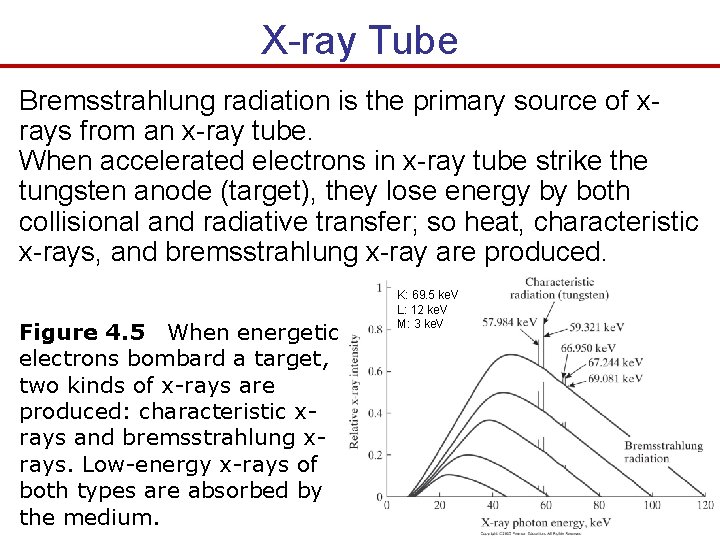

X-ray Tube Bremsstrahlung radiation is the primary source of xrays from an x-ray tube. When accelerated electrons in x-ray tube strike the tungsten anode (target), they lose energy by both collisional and radiative transfer; so heat, characteristic x-rays, and bremsstrahlung x-ray are produced. Figure 4. 5 When energetic electrons bombard a target, two kinds of x-rays are produced: characteristic xrays and bremsstrahlung xrays. Low-energy x-rays of both types are absorbed by the medium. K: 69. 5 ke. V L: 12 ke. V M: 3 ke. V